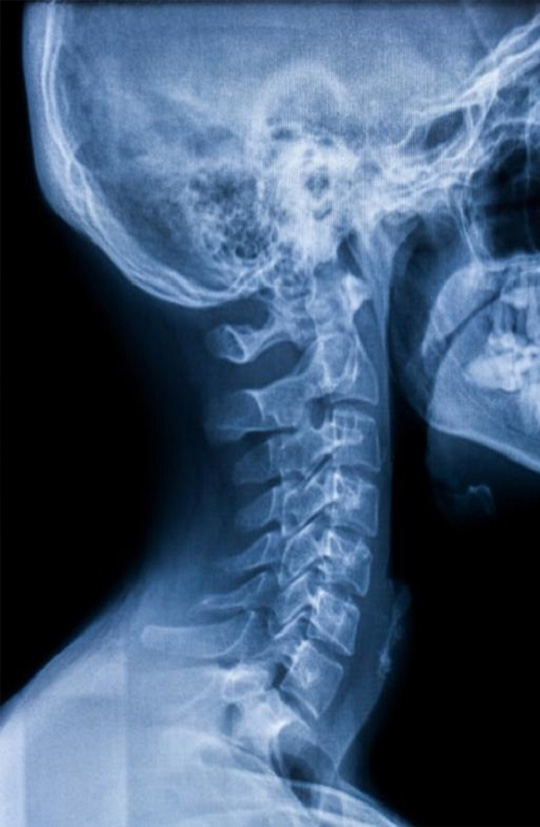

X-Ray

An x-ray examination creates 2D images of the body’s internal organs or bones to help diagnose conditions or diseases.

X-ray images contain information about the bones, soft tissue and air (lungs/bowel gas).